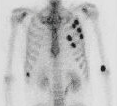

肺血流シンチ、肺換気シンチの役割と仕組み

心筋梗塞の危険性を調べる心筋シンチグラフィ(心血流シンチグラフィ)の役割

乳癌の転移を調べる骨シンチ検査とは?どのような仕組みで何が分かるのか?